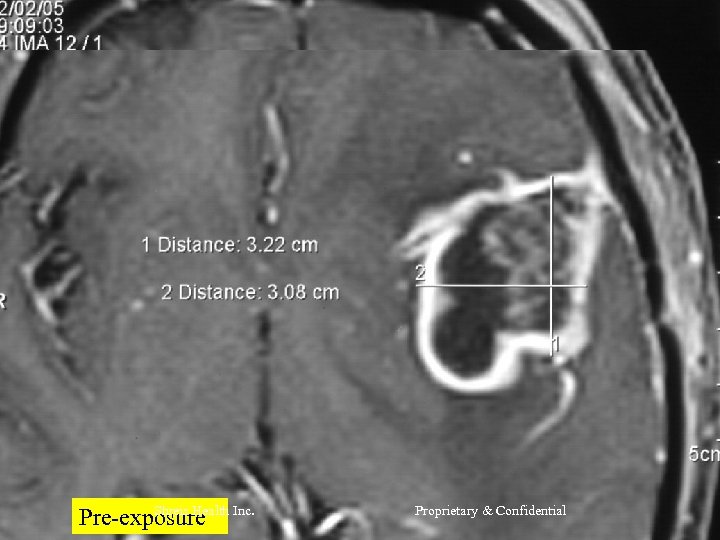

CASE 2 Mr R, 56 yrs l Nov 2004 – MRI Brain = Left frontal SOL (4 x 3 cm) - SX = Craniotomy x decompression of insular glioma HPR = Glioblastoma Grade IV l RT – 60 Gy/30 # till Jan 2005 l CT – Temedol x 2 # till Feb 2005 l Shreis Health Inc. Proprietary & Confidential

l l Presented Feb 05 - Loss of memory - Apathetic - Hemiparesis ® (power 3/5) Today after 1 course of RFQMR - No focal/Gen Neuro deficit - Normal higher functions and back to work. Shreis Health Inc. Proprietary & Confidential

Shreis Health Pre-exposure Inc. Proprietary & Confidential

Shreis Pre-exposure. Health Inc. Proprietary & Confidential